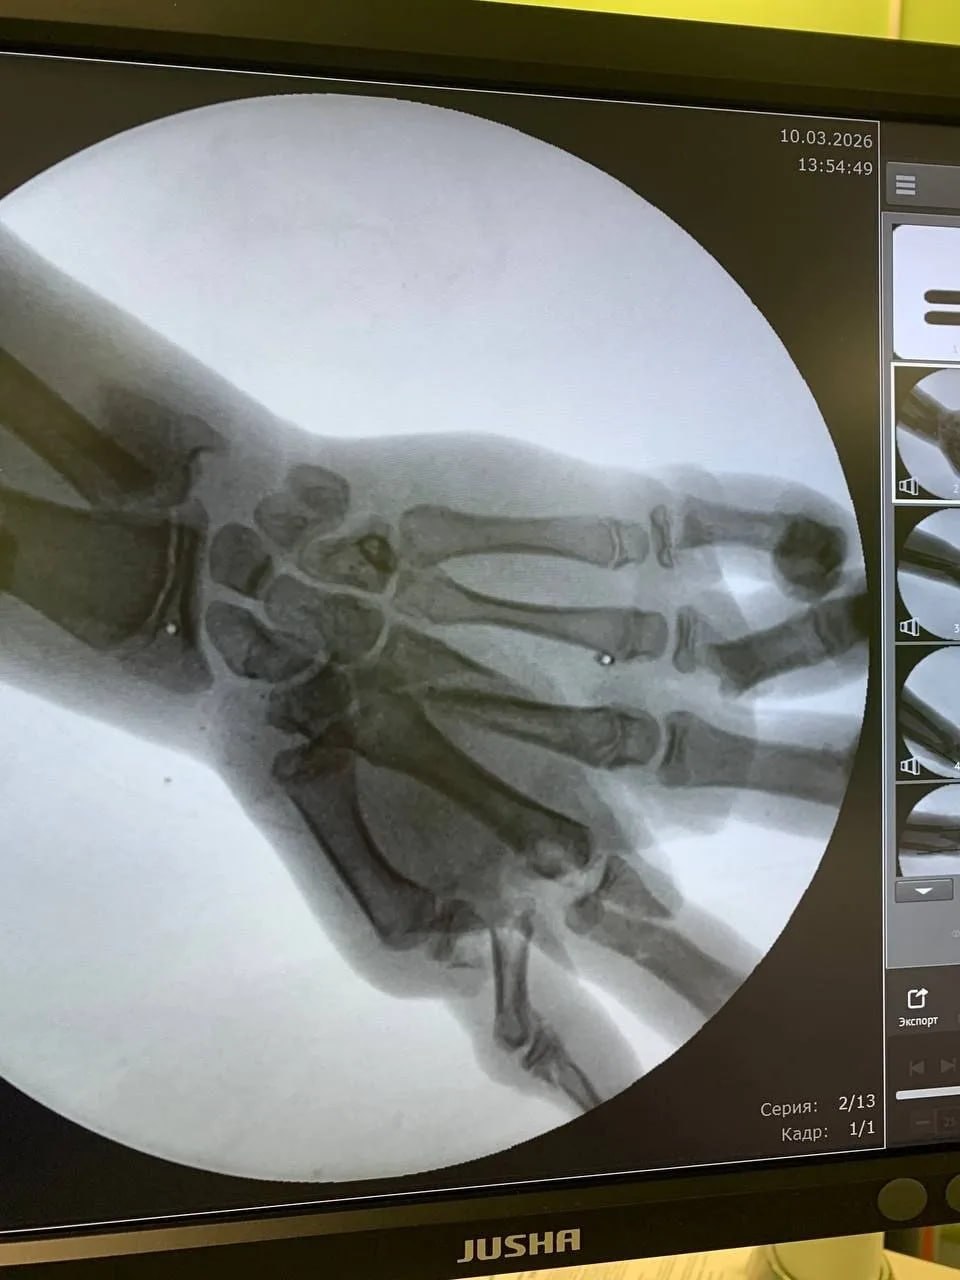

Подростка доставили в Детскую областную больницу в шоковом состоянии. У него были множественные переломы, кровотечение и опасность потерять кисть.

Команда хирургов провела две сложные операции: остановили кровотечение, собрали кости кисти и восстановили повреждённые ткани. Благодаря профессионализму врачей руку удалось сохранить.